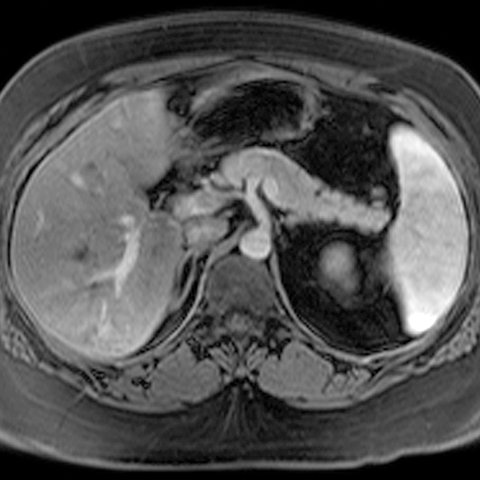

Normal Pancreas, Axial MRI [2 of 3]